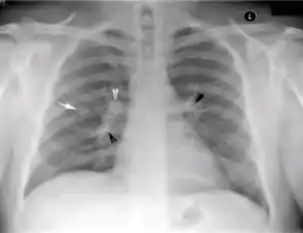

Chest X-ray of a person with advanced tuberculosis: Infection in both lungs is marked by white arrow-heads, and the formation of a cavity is marked by black arrows.